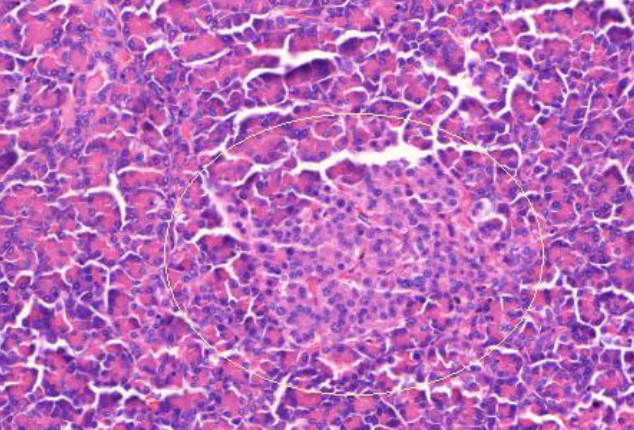

2. Pâncreas normal

1. Preto:ducto pancreático

1. Verde: ácino pancreático

1. Ilhotas de Langerhans

1. Lóbulos divididos por septos e gordura